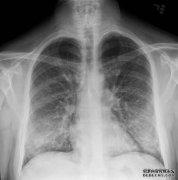

所有患者肺液样本均检出维生素E乙酸盐。 最新调查结果显示,专家们终于找到了一个有力的竞争者,来解释电子烟爆发的原因。电子烟爆发...

截至上周,美国神秘的电子烟疫情已导致近1,300人肺部受伤,26人死亡,其中包括一些看似健康的年轻人。但是是什么让这些疾病如此严重,...

随着与电子烟有关的疾病的神秘爆发持续增加,一项新的研究进一步揭示了可能导致人们生病的原因。 随着美国与电子烟有关的疾病神秘爆...

全国超过四分之三的患者报告使用含有四氢大麻酚的蒸汽产品。 经过数周的调查,美国出现了一起与电子烟有关的肺部疾病的神秘爆发美国...